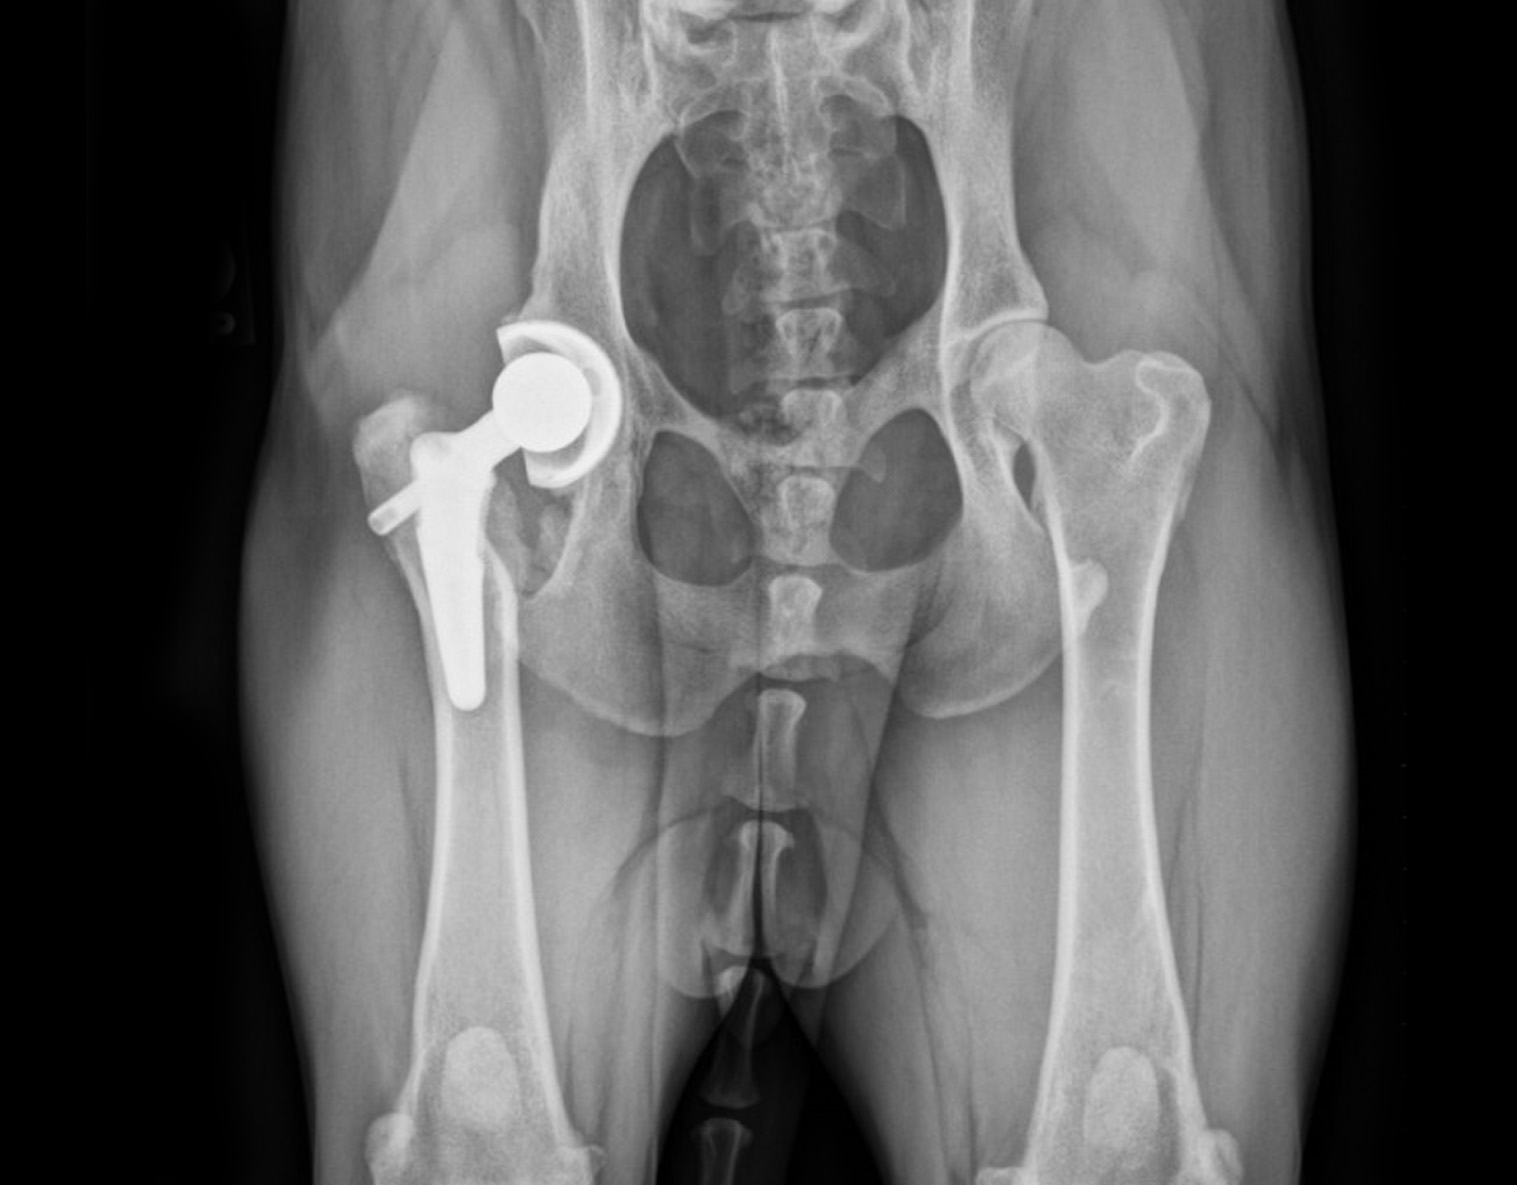

Date of Surgery: July 10, 2018

Product: BFX® Hip with Lateral Bolt Stem

Surgeon: Dr. Jonathan Dyce; The Ohio State University Veterinary Medical Center, Columbus, Ohio

“Bailey was rescued when she was approximately 2 years old. Her owner noticed hind-limb lameness and had her evaluated. X-rays revealed a fractured hip at which time a Femoral Head Ostectomy (FHO) was performed. Bailey healed well and lead an active lifestyle for 4 years before pain returned. She was then referred to Dr. Dyce who confirmed she was a good candidate for Total Hip Replacement. The surgery was successful and now, at 4 years post-op and 10 years of age, Bailey acts like a young pup! She goes on 12 mile runs with no apparent pain or issues, plays fetch with reckless abandon, leaps, and jumps.”